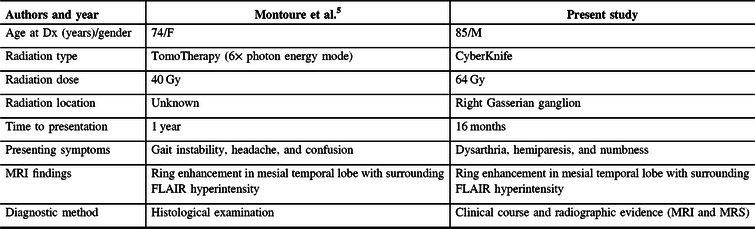

A literature review identified one previously reported case of radiation necrosis following stereotactic radiosurgery for trigeminal neuralgia.Reference Montoure, Zaidi, Sheehy, Shetter and Spetzler5 In Montoure et al.’s report, the patient had undergone TomoTherapy for trigeminal neuralgia 1 year prior to the development of a ring-enhancing lesion in the mesial temporal lobe (Table 1). The authors performed a supratotal resection of the lesion and a final diagnosis of radiation necrosis was made based on histological examination. When comparing the two cases, a number of differences and similarities are noted. Both patients were treated with stereotactic radiosurgery for refractory trigeminal neuralgia. Montoure et al’s case involved a total of 40 Gy of TomoTherapy radiation in two equally divided doses; our patient underwent a total dose of 110 Gy of CyberKnife radiation divided in two unfractionated doses 2 years apart; the mesial temporal lobe, depending on the location, received up to 5.5 Gy on the first treatment and up to 33 Gy in the second treatment – after analyzing the radiosurgery treatment plans, it appears that the area of suspected radiation necrosis likely received minimal radiation from the first treatment and up to 11 Gy from the second treatment (Figure 1). Both patients developed symptoms within 1–2 years. MRI findings were nearly identical. Montoure et al.’s case was diagnosed with tissue biopsy, while this case was diagnosed by a combination of clinical characteristics and radiographic evidence (MRI and MRS). A comparison is summarized in Table 1.

Table 1: Comparison of cases from literature review